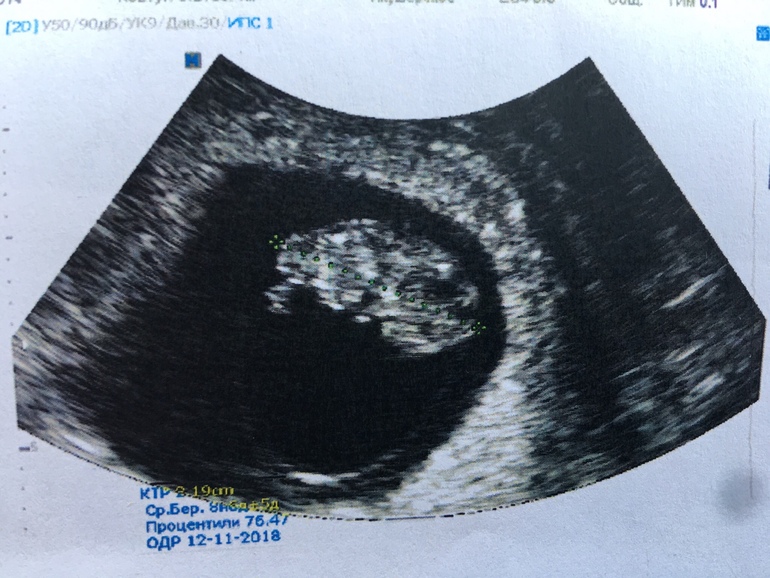

УЗИ 8 недель

На пути к мечтеВот и сходили мы в ЦИР на УЗИ в 8недел 4 дня

КТР - 22 мм, соответствует 8 нед 6 дней

169 уд/мин

Желточный мешок 4мм

Расположен хорион по задней стенке

Рубец на матке 6,9мм

ЖТ в ЛЯ 20мм